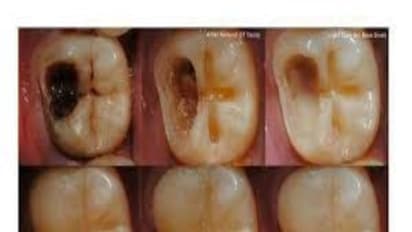

பாக்டீரியாக்கள் பற்களை சொத்தையாக்கிவிடும். இப்படி சொத்தையான பற்களை ஆரம்பத்திலேயே கவனிக்காமல் விட்டால், பற்களில் பெரிய ஓட்டை உருவாகி, நாளடைவில் ஈறுகளில் நோய்த்தொற்றுகள் ஏற்பட்டு, அதுவே பல பிரச்சனைகளை உண்டாக்கிவிடும்.

அதற்காக சொத்தைப் பற்களை பிடுங்கி எடுக்க வேண்டும் என்பதில்லை. பற்களின் பின்னால் உள்ள கறைகளைப் போக்கினாலே போதும்.